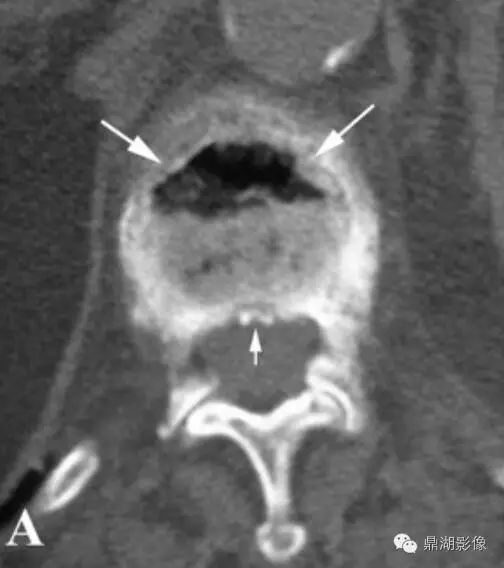

我院CT图像:

腰椎多发压缩性骨折,骨质疏松,腰2椎体真空裂隙征;

CT:可以看到真空征,同时骨质表现出蛋壳样改变。

真空裂隙征(IVC):是椎体缺血坏死的典型表现,前部较后部多见;IVC为渗液时,T1低信号,T2高信号,此征象称为液体征象,高度提示椎体缺血坏死,并可用于鉴别kummell与骨质疏松引起的压缩性骨折,IVC为气体时,MRI均为低信号。